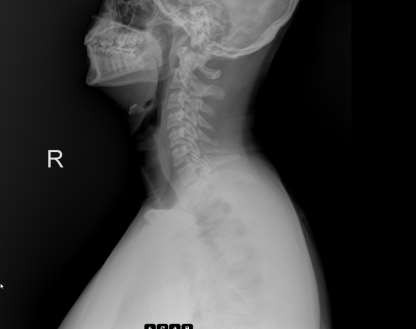

2 adet resim ekleyeceğim. Birisi 2020 yılında çekilen görüntü.

Diğeri de dün yani 31/12/2024 tarihinde çekilen görüntüdür.

İkisi arasında fark net olarak görünüyor. 3 yılda ağdakinden sola dönmüş. Allaha şükür boyunluk ile 1.5 - 2 aya düzelebilecek bir durummuş. Ayrıca ortopedik yastık kullanmamı söyledi doktor.